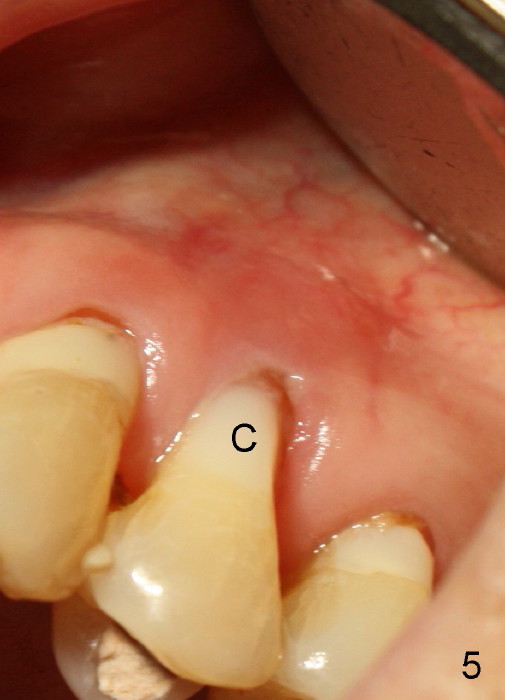

A month later, the fistula disappears (Fig.5). Effort is exerted without success to find the obliterated canal, including increasing access and removing the portion of composite which may block the opening of the canal. RCT is finished. Two months postop, the patient returns for prophy. She remains asymptomatic. There is no recurrent infection. Seven months post RCT, periapical radiolucency seems to have disappeared (Fig.6), whereas the fistula does not recur (Fig.7).